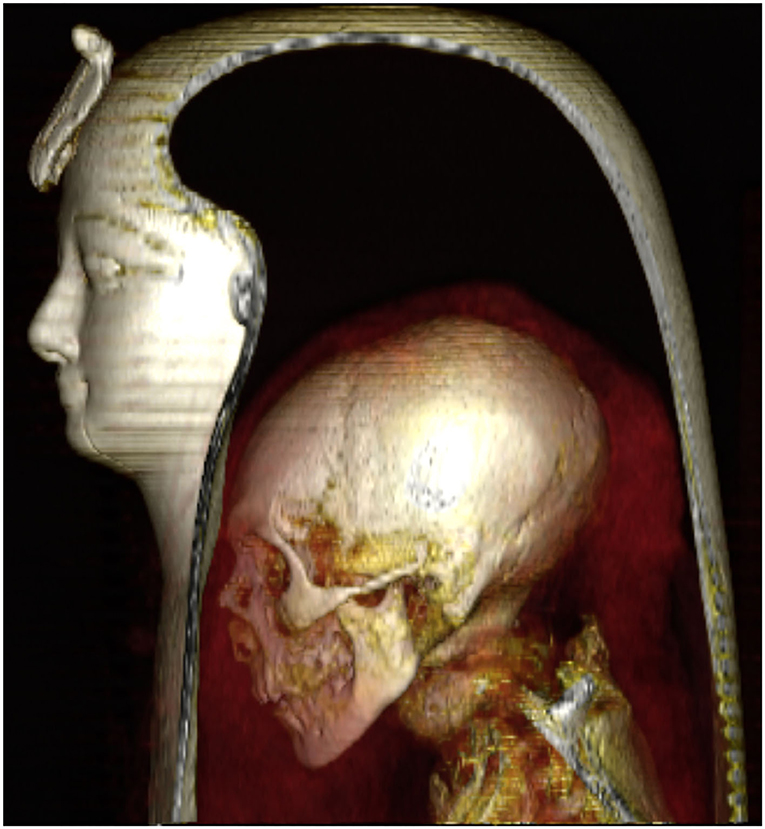

Researchers have used digital technology to take the first accurate look inside the mummy of King Amenhotep I, which has remained unwrapped in modern times, according to a study published on Tuesday.

The scans revealed details about the appearance and mummification of the 18th Dynasty king, who ruled Egypt from about 1525-1504 BC and was the son of New Kingdom founder Ahmose I.

Amenhotep’s mummy, adorned with decorations on its linen wrapping and its funerary mask, was found along with those of other kings and queens in a cache in Luxor in 1881 and transferred to Cairo.

In 2019, Egyptologist Zahi Hawass and Cairo University professor Sahar Saleem used a computed tomography (CT) machine to “digitally unwrap” the mummy before it was moved to a new collection at Cairo’s National Museum of Egyptian Civilization.

The results of their study, published on Tuesday, showed that Amenhotep’s face resembled that of his father, and estimated his age at death to be 35 years, though no cause of death was clear, according to a statement from Egypt’s antiquities ministry.

It appeared to show that he was the first king to be embalmed with his forearms crossed on his body, and proved that his brain was not removed, unlike those of most New Kingdom kings.